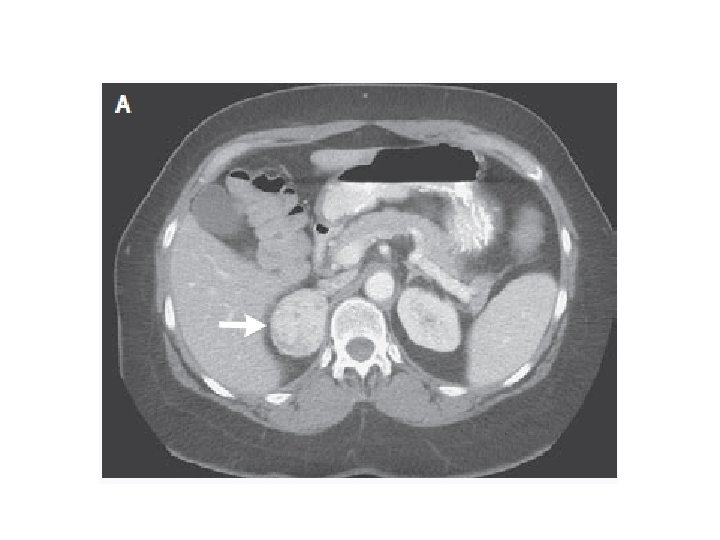

MASA SUPRARRENAL

¿Maligno o benigno?

¿es funcionante?